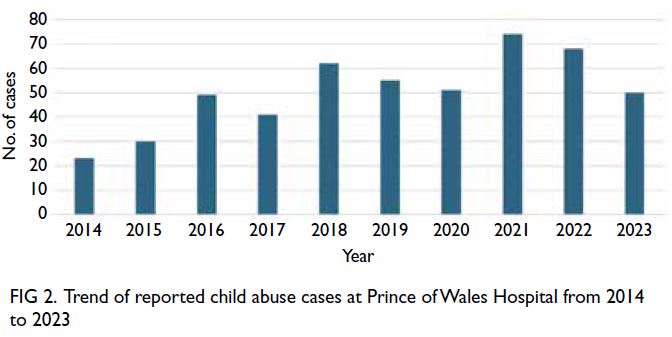

In total, 503 reported cases of child abuse were

included in the study. The number of reported cases

showed an upward trend over the 10-year period,

from 23 cases in 2014 to 50 cases in 2023 (Fig 2).

The case distribution is presented in Table 1.